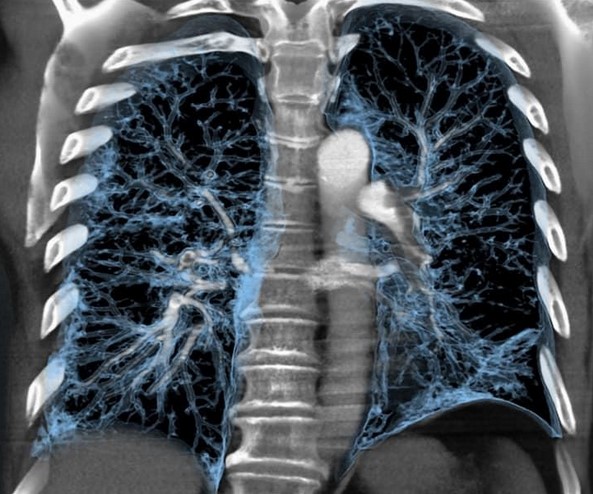

Фотографии и снимки КТ легких без контрастных веществ

Раздел: Визуальный дайджест